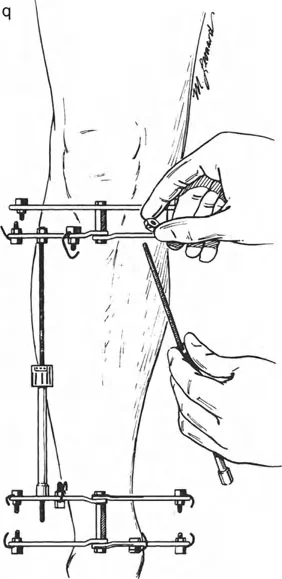

على العكس من ذلك، إذا تم استخدام دبابيس نصفية (مسامير شانز)، فإنها تقيد العظم بطبيعتها بالحلقة. نظرًا لأن الدبابيس النصفية هي أذرع صلبة (مثبتة من طرف واحد بالحلقة ومغروسة في العظم من الطرف الآخر)، فإنها لا تسمح للعظم بالانزلاق على طول محور السلك. هذا يجعل أسلاك الزيتون غير ضرورية للترجمة في منشآت الدبابيس النصفية، ولكنه يتطلب من الجراح التأكد من أن الدبابيس النصفية قوية بما يكفي (عادةً دبابيس بقطر 5 مم أو 6 مم مطلية بهيدروكسي أباتيت) لتحمل لحظات الانحناء الناتجة عن الترجمة.

نصائح جراحية للمنشآت القريبة من المفصل

| المبدأ | التطبيق السريري | تحذير / خطأ محتمل |

|---|---|---|

| التحقق من CORA | دائمًا تحقق من CORA الحقيقي في الأشعة السينية الطويلة للطرفين قبل بناء المفصلة. | الاعتماد على الأشعة السينية القصيرة للركبة سيؤدي إلى CORA غير دقيق وبالتالي سوء محاذاة. |

| ACA العمودي | تأكد من أن محور المفصلة (ACA) عمودي تمامًا على مستوى التشوه. | محور ACA مائل سيحدث تشوهًا ثانويًا غير مرغوب فيه (مثل تصحيح التقوس ولكن إحداث الانحناء الأمامي). |

| تخليص الأنسجة الرخوة | عند استخدام قاعدة قطع العظم 2، احسب الترجمة المتوقعة وتأكد من أن الأنسجة الرخوة يمكن أن تستوعبها. | عدم مراعاة الترجمة يمكن أن يتسبب في اصطدام العظم بالجلد، مما يؤدي إلى النخر. |

| تقابل الأسلاك | استخدم ما لا يقل عن سلكين زيتون متقابلين لكل قطعة إذا كنت تتجنب الدبابيس النصفية. | الأسلاك الزيتون الفردية ستسبب قصًا ودورانًا غير مرغوب فيه حول محور السلك. |